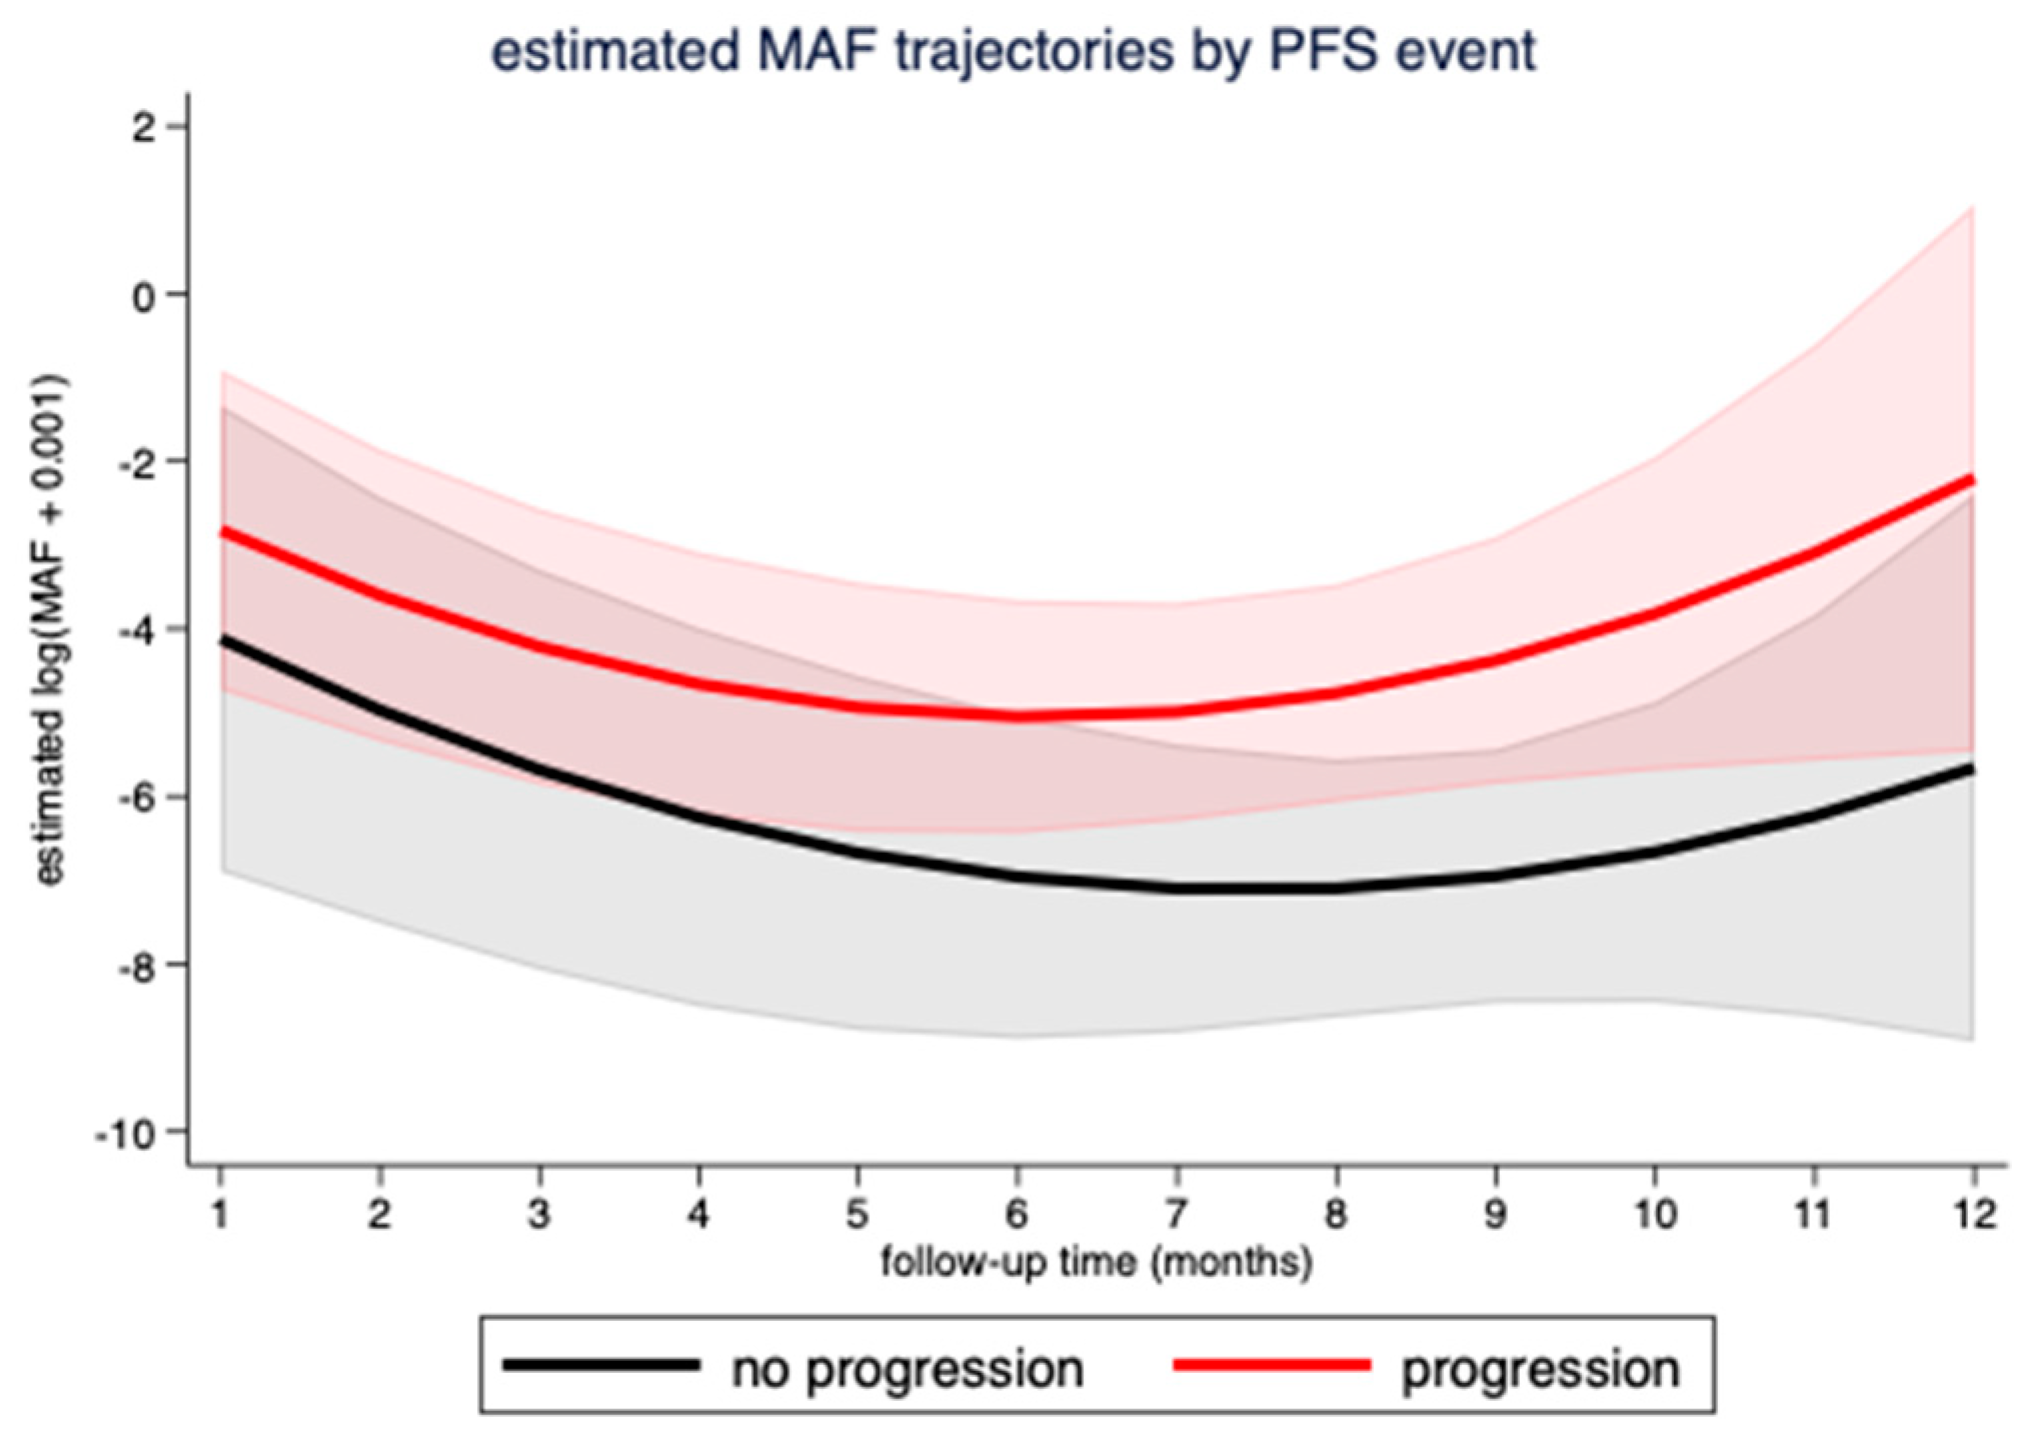

3.3. Correlation of MAF Levels with Radiological Response